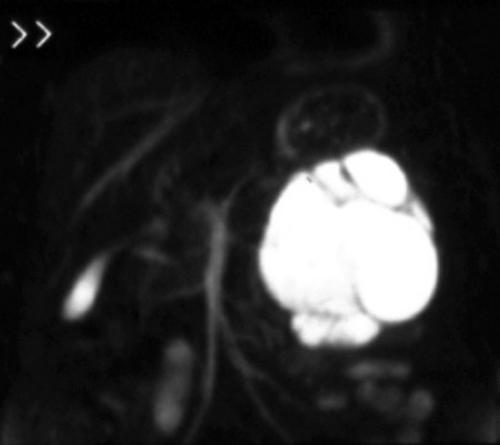

In symptomatic patients or when neoplasms are located within the pancreatic head, bilio-pancreatic duct abnormalities are frequently found. Bilio-pancreatic duct impairment is best depicted by MRCP. This technique does not require intravenous contrast agent administration and provides information similar to endoscopic retrograde cholangiopancreatography (ERCP) including stenosis, occlusion, and duct dilatation, with a high accuracy reported [6]. MRCP clearly identifies the site, extent and degree of the stenosis, and depicts segmental and/or diffuse bilio-pancreatic tree abnormalities related to the size and location of pancreatic neoplasms (Figure 3). Typical ductal changes secondary to pancreatic head neoplasms include: the double duct sign and the mouse tail sign. The former refers to dilatation of both the biliary and pancreatic ducts, the latter is due to the reduction of the bile duct caliber as a result of sudden obstruction at pancreatic head. Moreover, subtle ductal changes provided by MRCP often suggest the diagnosis of small, not well depicted pancreatic tumors and prove to be helpful in the differential diagnosis of chronic pancreatitis in which dilated side branches are seen within, rather than adjacent to, an inflammatory mass [7, 8]. Finally, MRCP, by demonstrating the level of biliary tract obstruction, provides an optimal biliary map useful for appropriate drainage approach (percutaneous cholangiography or ERCP).

Figure 3. a) MRCP shows distal obstruction of the common bile duct and pancreatic duct with upstream dilatation due to head pancreatic neoplasm. b) MRCP shows stenosis of the common bile duct with upstream dilatation due to an infiltrating pancreatic head neoplasm. The main pancreatic duct is slightly dilatated.